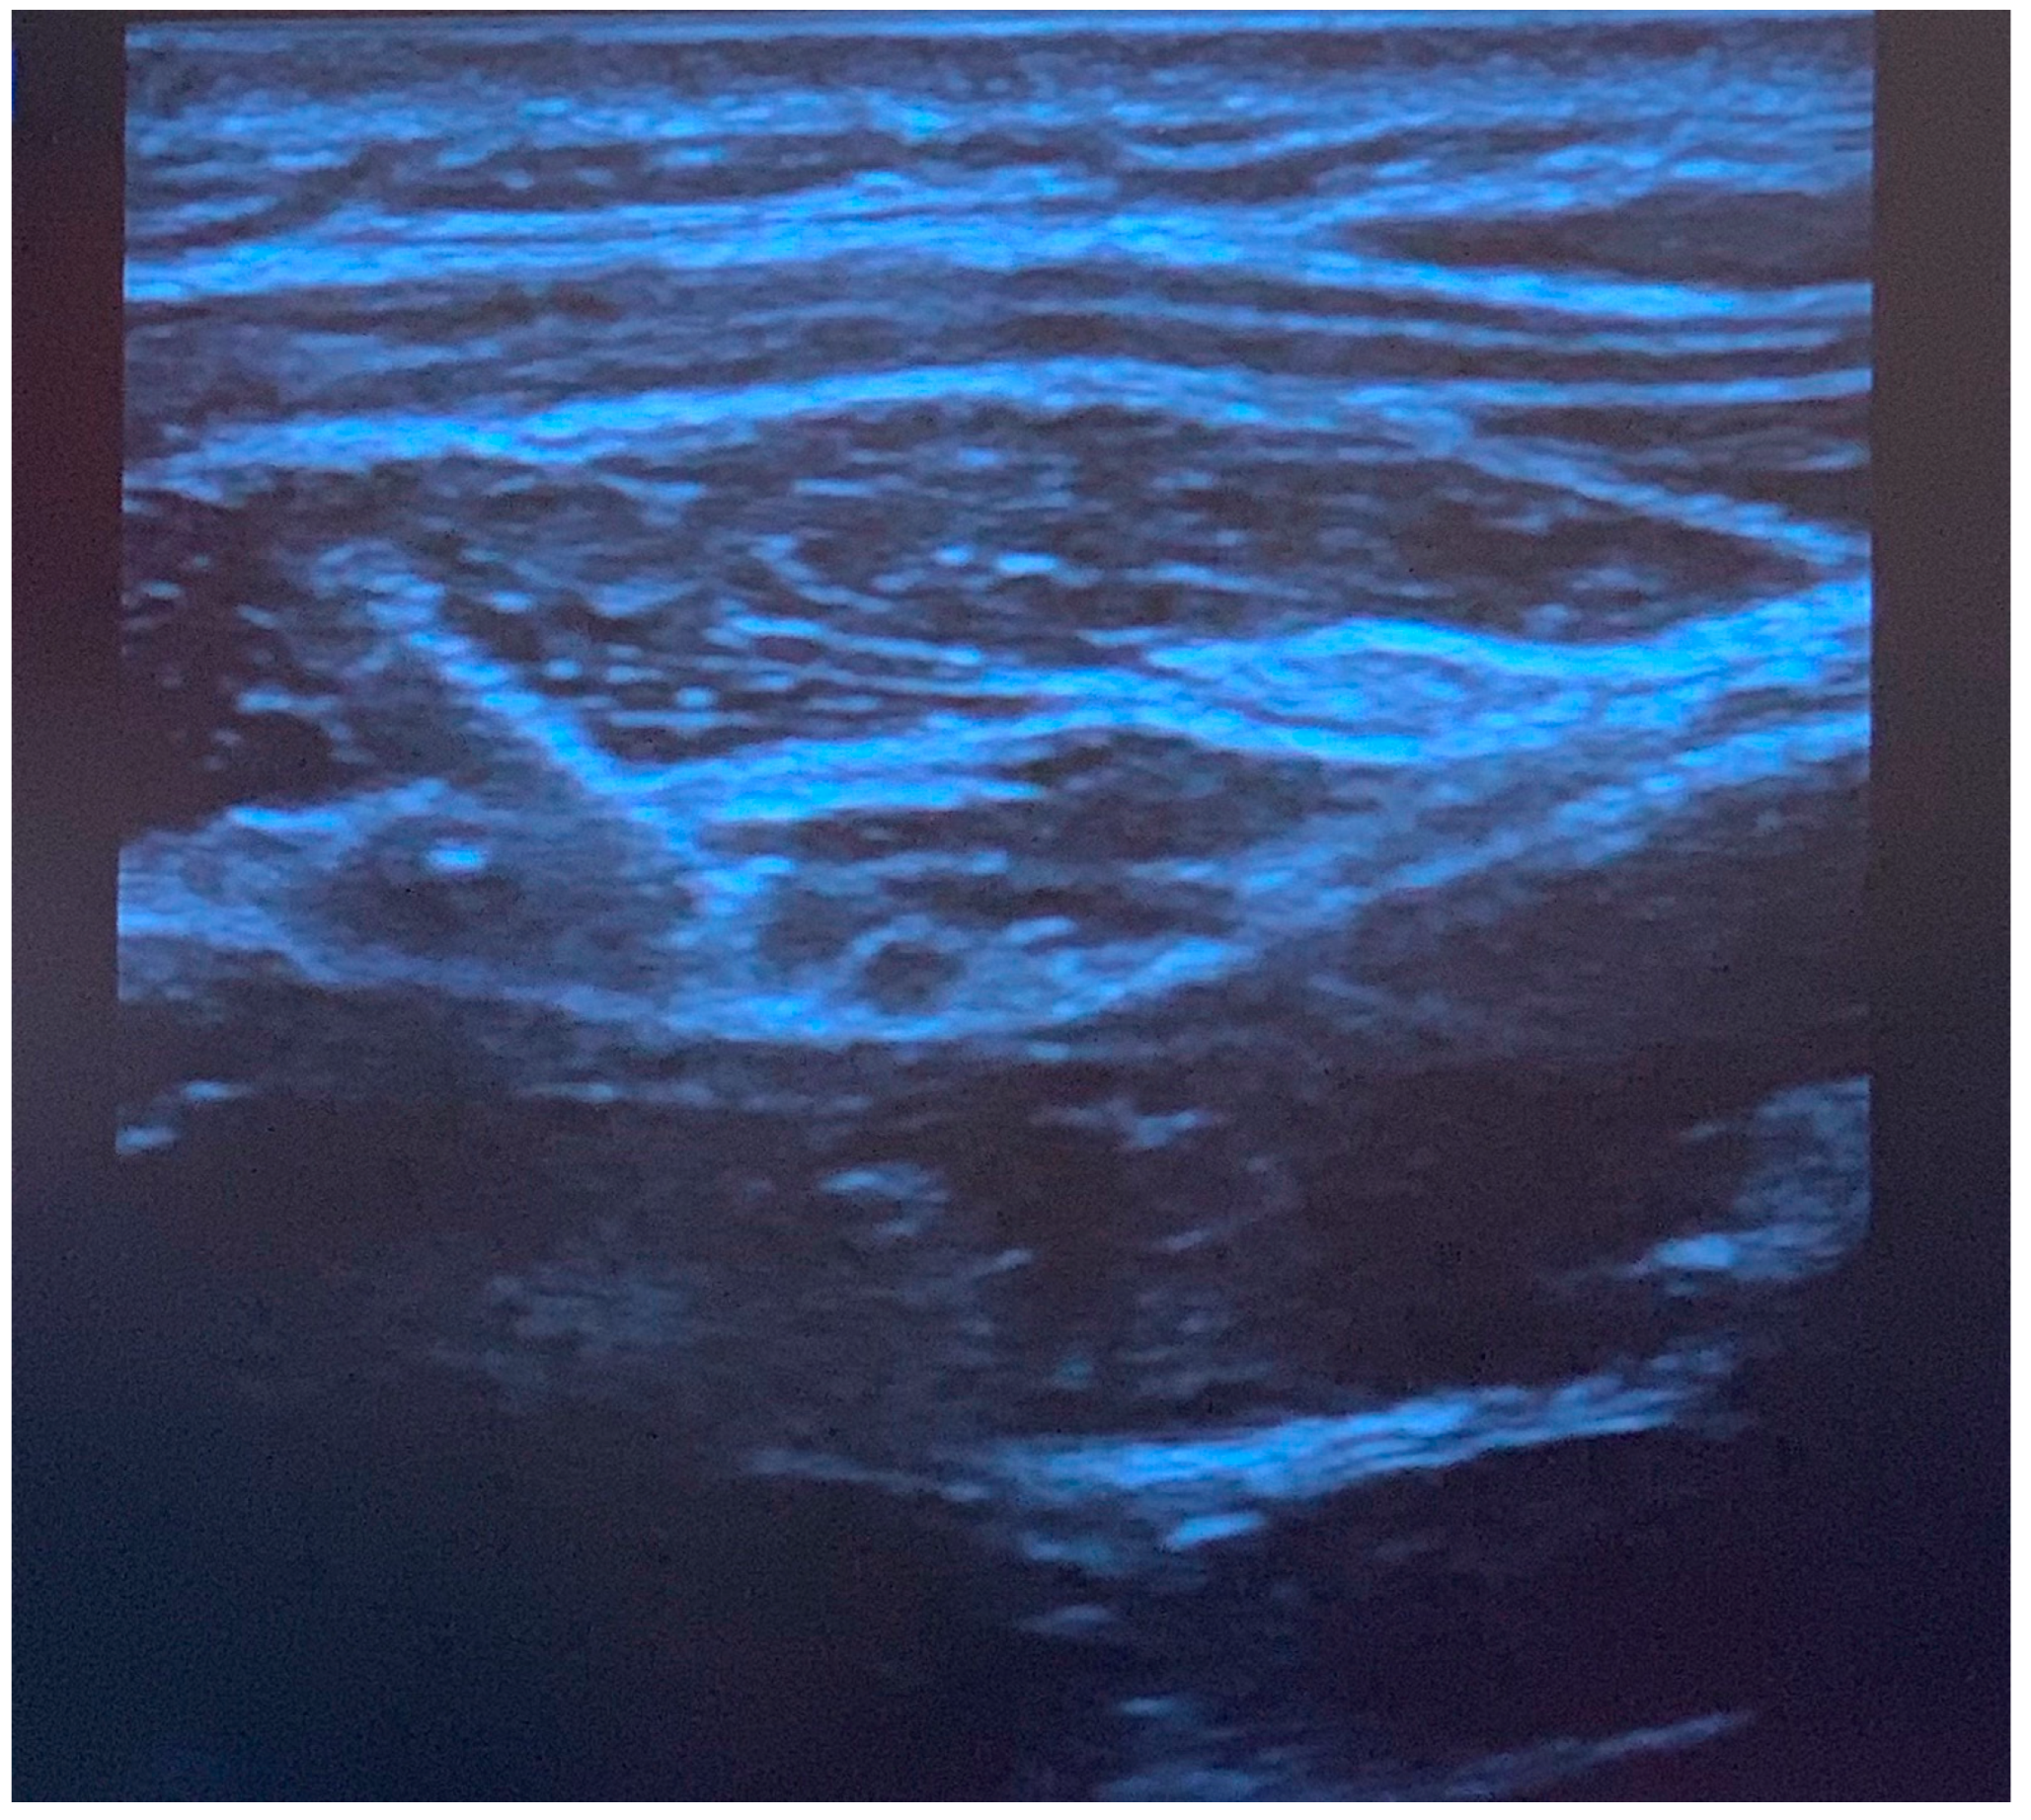

Greater occipital nerve blocks were performed following induction of anesthesia, prone positioning, and sterile preparation. To perform the blocks, a linear ultrasound probe was used to locate the C2 spinous process, and the probe moved laterally and rotated (Figure 1) to find the obliquus capitis inferior muscle plane (Figure 2) as previously described [6]. Blocks were performed with 0.2% ropivacaine, with volume and additives determined by the anesthesiologist. Prior to incision, additional injections of epinephrine with or without local anesthetic were performed at the incision site by the surgical team for hemostasis. Intraoperative analgesic and sedative adjunct usage was determined by the anesthesiologist. Further details of intraoperative characteristics and intraoperative medications can be found in Table 1.

Figure 2. Ultrasound image of greater occipital nerve block injection. The needle is positioned superior to the obliquus capitis inferior muscle, and local anesthetic spread is observed in the fascial plane. The semispinalis muscle is observed above the fascia.